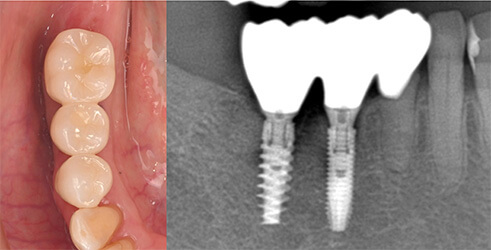

古い被せ物は色や形態が周りと合っておらず、また、被せ物の下には虫歯もありました。

期間はかかりましたが、患者様に非常に喜んで頂きよかったです。